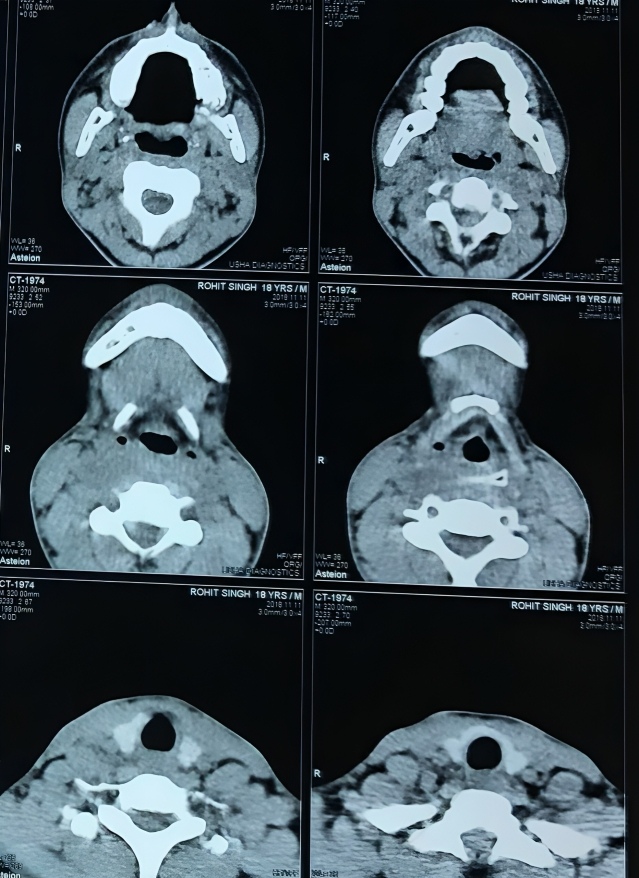

Experience expert, reliable and compassionate ENT care when it matters most. Dr. Ashok Garje delivers advanced diagnosis and specialized treatment for ear infections, nasal obstruction, throat disorders, hearing loss and sinus diseases - ensuring precise care, faster recovery and long-lasting relief for every patient.

Comprehensive care for ear infections and hearing loss, including Tympanoplasty, Mastoidectomy, Ossiculoplasty and Stapedotomy/Stapedectomy for improved hearing outcomes.

Advanced treatment for nasal blockage, sinus disease, allergies and watery eyes with Endoscopic Sinus Surgery, Septoplasty, Rhinoplasty, Dacryocystorhinostomy and Endoscopic DCR.

He is skilled in endoscopic evaluations, minimally invasive ENT procedures, vertigo assessment and advanced ear - nose - throat care, ensuring precise and patient-friendly treatment.